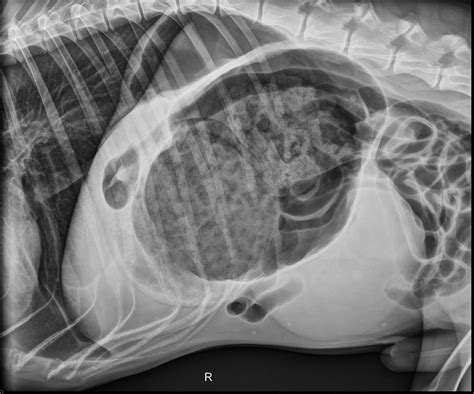

Distended Abdomen Dog

A distended abdomen in a dog refers to an enlarged or swollen belly. This condition can be caused by a variety of factors, including dietary issues, gastrointestinal problems, or more serious medical conditions. Recognizing the signs and understanding the potential causes can help you take the right steps to address the issue.

• Imaging Studies: X-rays, ultrasounds, or CT scans can provide detailed images of the abdominal organs and help identify the cause of the distension.